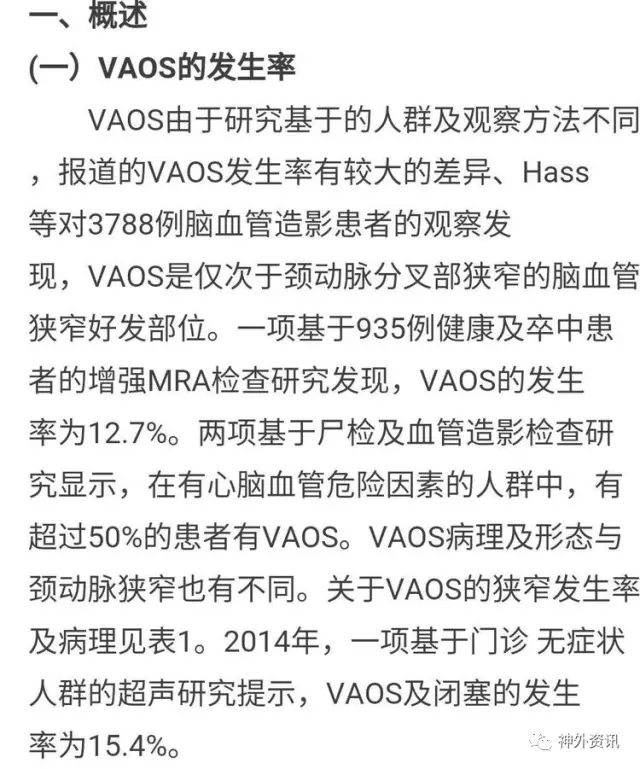

2014版VA狭窄指南:椎A开口狭窄在心脑血管病高发人群中可达50%,这么高的比例还是要高度重视,临床上TCD、CTA/MRA确可诊断。

2014版VA狭窄指南:文献提示VA支架后再狭窄达11-30%,所以VA内膜剥脱术对于症状性闭塞和狭窄还有技术应用的空间。

2014版VA狭窄指南:VA再狭窄目前认为主要与开口段狭窄段的长度有一定正√相关,与支架种类、扩张压力、局部开口段迂曲度有一定相关性。

2014版VA狭窄指南:外科治疗VA狭窄并非一线干预方法,但我们可以给支架植入失败和症状性支架内再狭窄或闭塞患者提供终极治疗方案,面对病人我们应当提供序贯性的治疗,天下大同,内外一家,解决的病人疾病之苦痛。